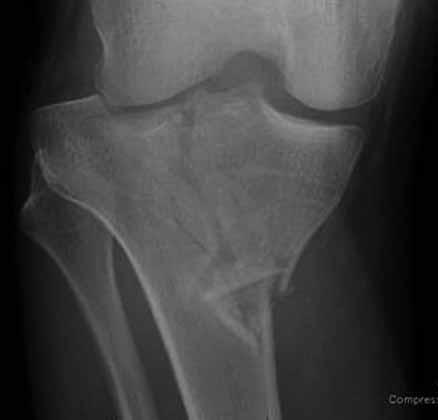

На снимке типичный перелом медиального тибиал плато с передним смещением (подвывих) по Schatzker IV. Консервативное лечение без медиальной опоры не может удержать деформирующие силы, и из-за вторичного смещения мыщелка конечность смещается в варус. Кроме передних смещений еще встречаются сложные фронтальные варианты переломов, и тогда голень подвывихивается кпереди.

А в данном случае мыщелок сросся со смещением кпереди и ротирован. За счет интактной наружной колонны опороспособность конечности сохранена, но остается варус и экстензия конечности. Для предоперационного расчета необходимо сделать на всю длину конечности рентгенограмму, а в остром периоде КТ и 3-мерный снимок помогут лучше ориентироваться в характере перелома.

Остеотомия с разворотом медиального мыщелка, и для фиксации можно применить параллельные субхондральные межмыщелковые шурупы. Дополнительная медиальная Smith-Nephew PERI-LOC™ (Periarticular Locked Plating System) пластина. При отсутствии специальной пластины можно адаптировать Tomofix для высокой остеотомии. Доступ прямой медиальный через pes anserinus или через интервал pes с medial gastrocnemeus.